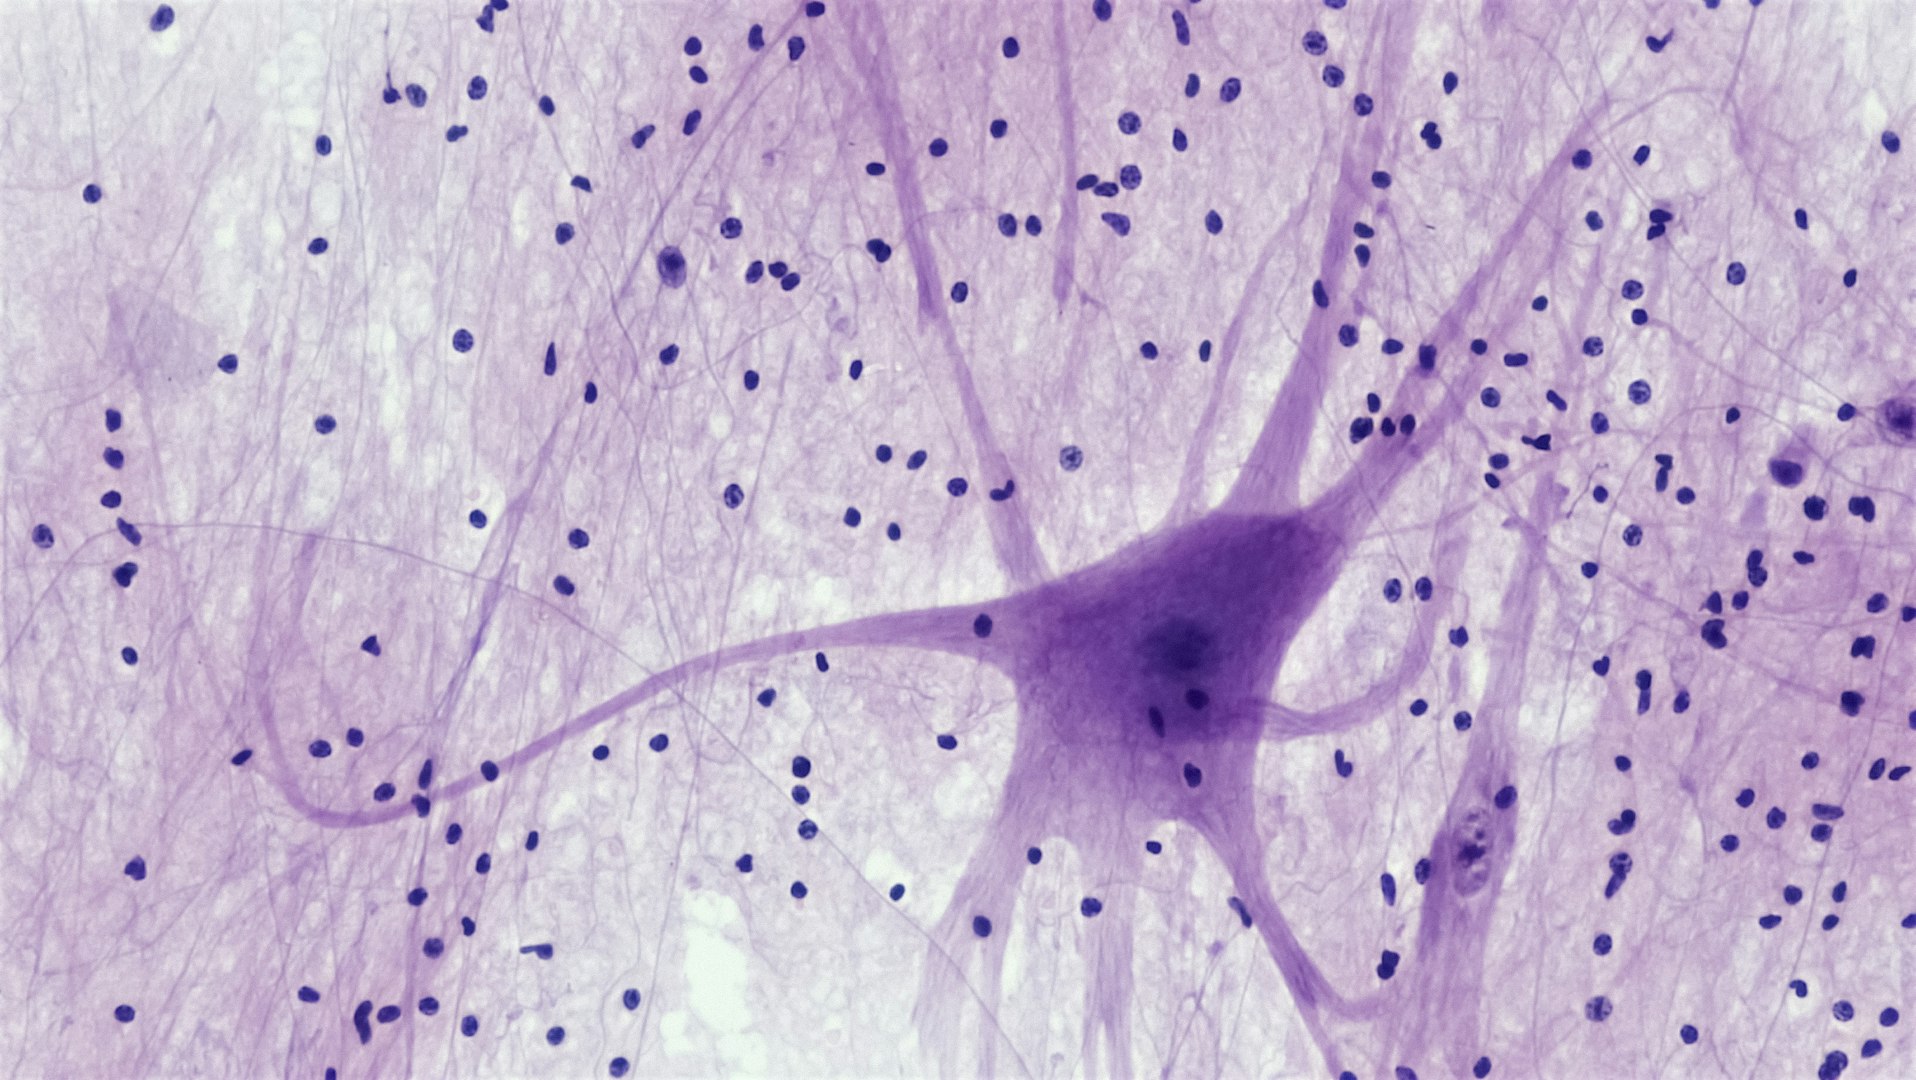

What is Fascia or Connective Tissue?

Fascia or connective tissue is located underneath your skin; it forms a continuous net throughout your entire body, similar to the pith of an orange.

Surface Fascia is located directly beneath the skin and Deep Fascia surrounds muscles, tendons, joints, ligaments, organs/organ systems. It has a crucial role in supporting the body

Within areas of injury, little use (sedentary lifestyle), over use and even old age, the fascia can become dehydrated, making it difficult for water to flow through connective tissue.

Injured or Dehydrated fascia can begin to restrict mobility, create inflammation, pain and stiffness; weakening your healing response.

In Bowen Therapy, a cross-fibre 'Bowen move' is applied accordingly to strategic locations on the fascial planes and junctions, influencing the fascial mechanoreceptors (sensory nerve endings in the fascia) creating body heat and bio-electric energy, allowing the fibres to separate, activating hydration in the bodies tissues and activating your bodies own healing response or homeostasis.